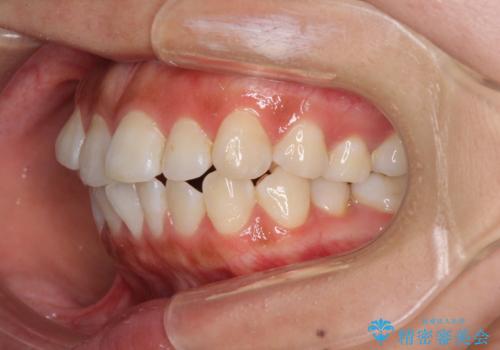

しっかりと装着時間を遵守してくださったので、思い通りの歯列に整えることができました。

結婚式前に終了させることができ、患者様には大変満足していただきました。